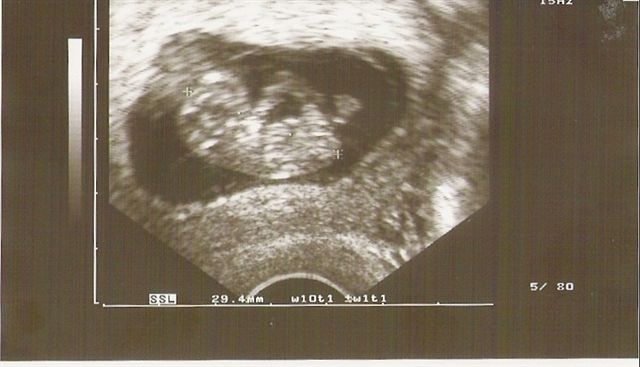

So heute war mein Termin habe meinen Mutterpass bekommen,oh man es ist so ein wunderschönes Gefühl Man kann schon beinschen und Ärmchen sehen,und zugelegt habe ich auch ganz schön Am 15.01 habe ich meinen nächsten Termin Ab Morgen bin ich wieder Arbeiten mal gespannt was auf mich zu kommt.Nur habe ein kleines Problem mein Arbeitsvertrag geht bis zum 15.05 habe aber erst am 1.08 ausgezählt steht mir Arbeitslossengeld zu?Obwohl ich hoch schwanger bin ?Muss mich mal erkundigen. :dance:

beweiss.

Dateianhänge

Scannen.jpg